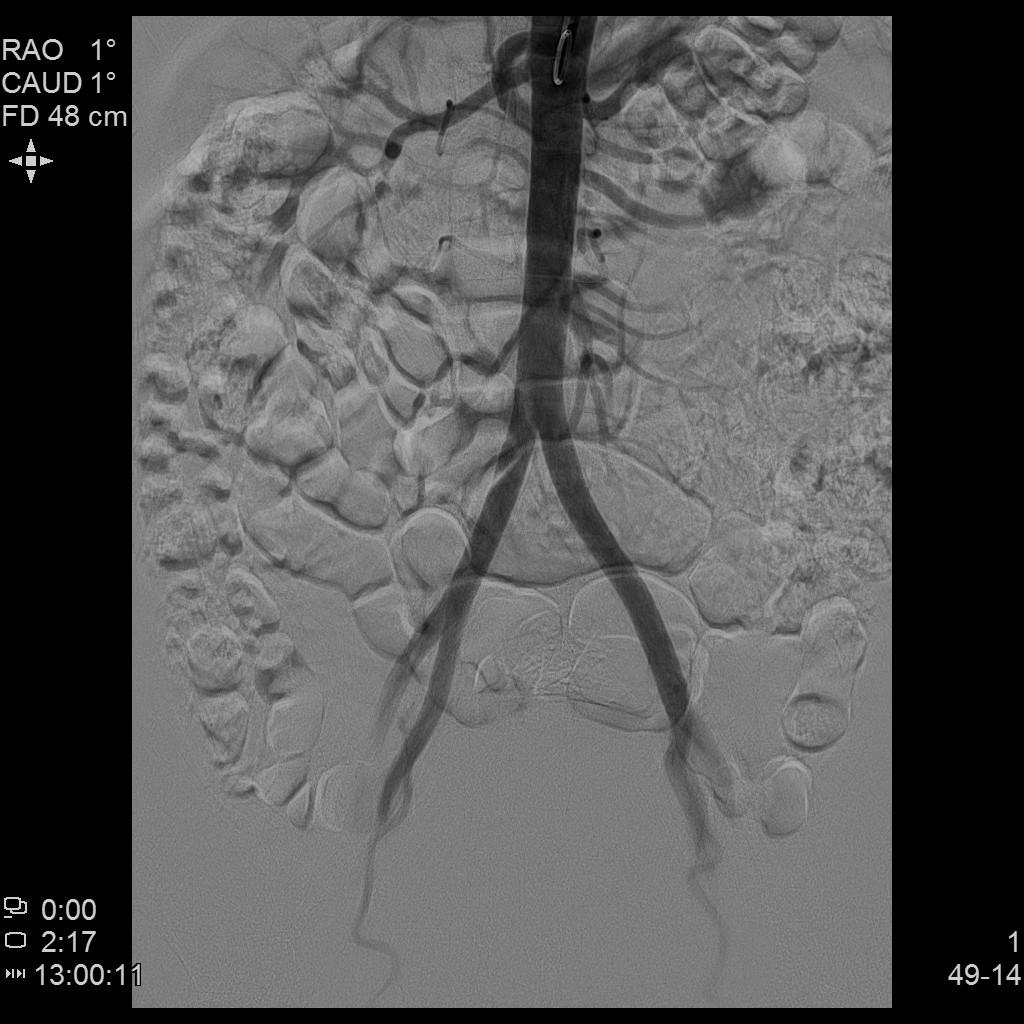

腹主动脉造影